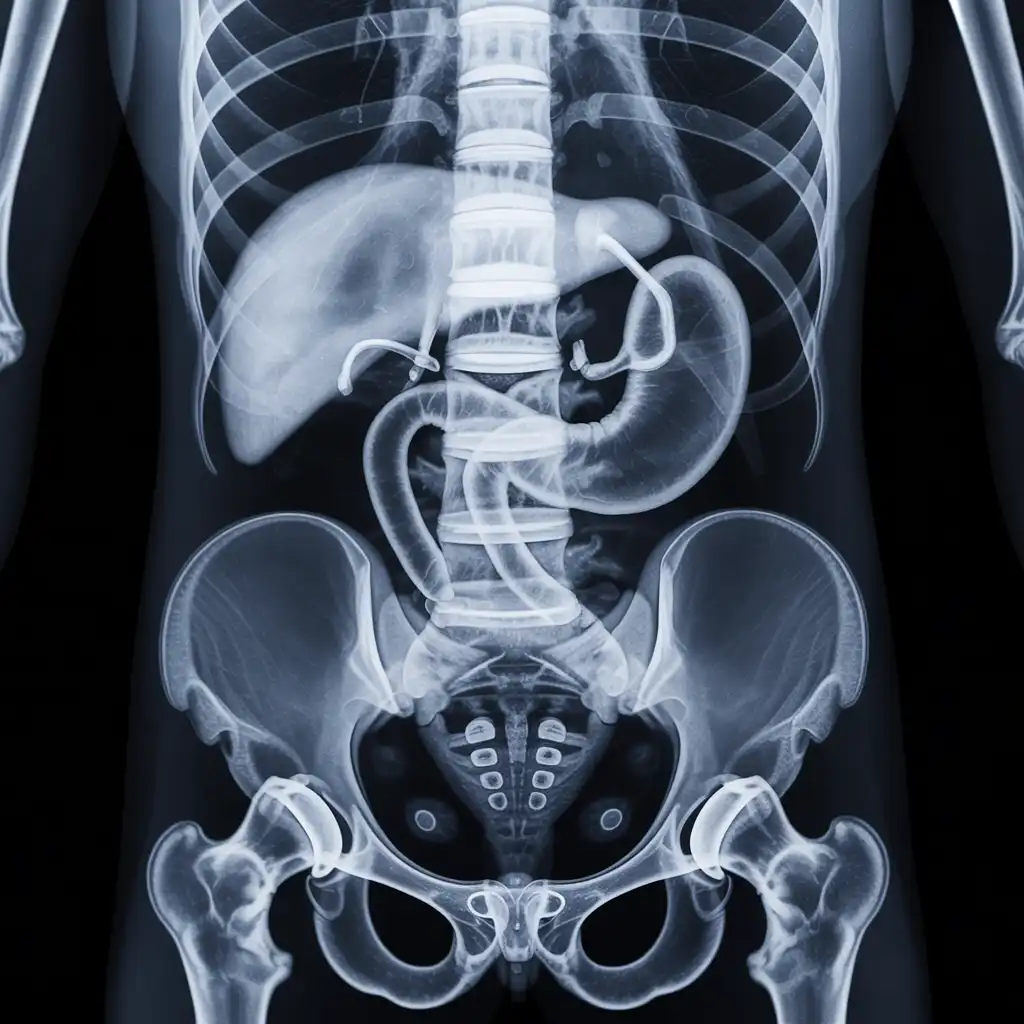

Una lastra a domicilio è una radiografia eseguita direttamente a casa del paziente, grazie all’intervento di un tecnico sanitario qualificato dotato di apparecchiatura digitale portatile.

L’esame viene effettuato sul posto, senza necessità di spostare la persona dal letto o dalla poltrona, e garantisce una qualità diagnostica paragonabile a quella di un reparto ospedaliero.

Una volta acquisite, le immagini vengono trasmesse al medico radiologo, che le analizza e redige il referto in tempi brevi.

Nel corso degli anni abbiamo effettuato migliaia di radiografie a domicilio in abitazioni private, RSA, centri di assistenza e strutture per anziani, utilizzando apparecchi digitali portatili certificati che garantiscono immagini precise e tempi di esecuzione rapidi.